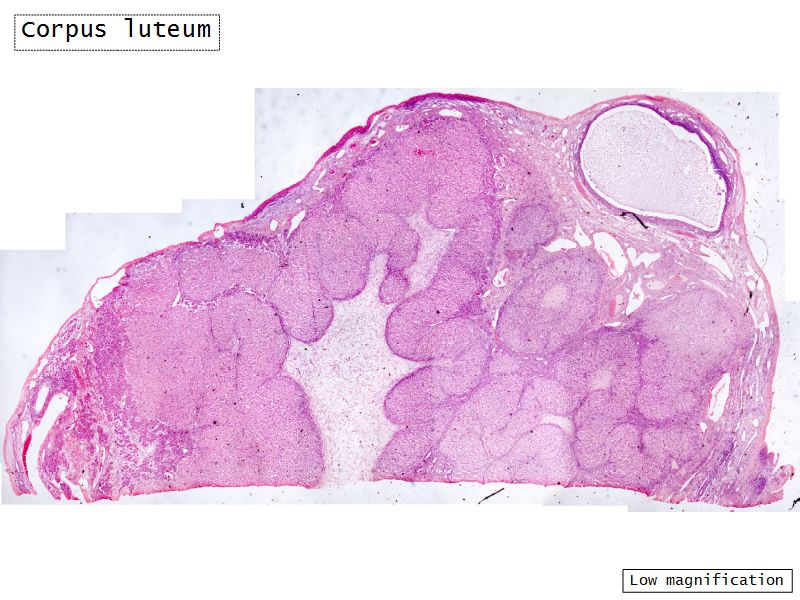

Corpus luteum

Slide 91

Corpus luteum

- Two major cell types

- Granulosa lutein cells

- modified granulosa cells

- Theca lutein cells

- modified theca interna cells

- Many capillaries